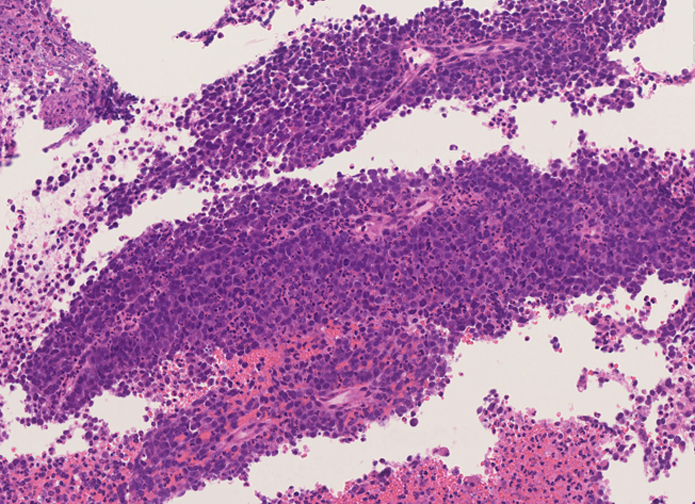

副鼻腔腫瘤生検組織

日本病理学会中部支部交見会のスライドより。(S.Suzuki Dr.)

NUT03.jpg NUT04.jpg

詳細は以下のcase reportをご参照ください。

Suzuki S, Kurabe N, Minato H, Ohkubo A, Ohnishi I, Tanioka F, Sugimura H.

A rare Japanese case with a NUT midline carcinoma in the nasal cavity: a case report with immunohistochemical and genetic analyses. Pathol Res Pract. 2014 Jun;210(6):383-8. doi: 10.1016/j.prp.2014.01.013. Epub 2014 Feb 22. PMID:24655834